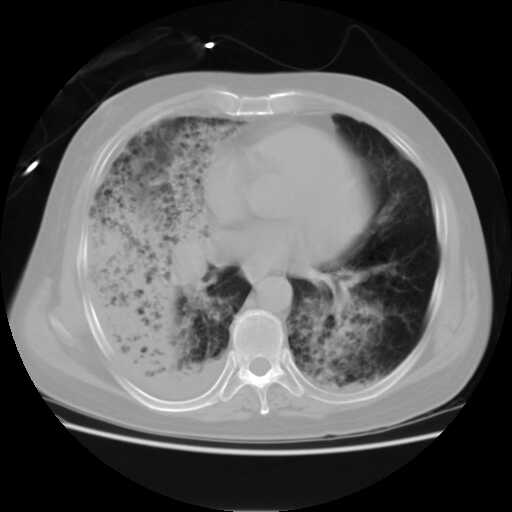

患者,男,60岁,病史如下:

2008.8.11胸片

病变从8.11-8.17明显改变,增多,以蜂窝状改变为主,类蜂窝肺,似弥漫性肺泡癌,但是病变进展太快,不符合弥漫性细支气管肺泡癌。因此考虑为特殊微生物感染,多以霉菌类常见,建议细菌微生物学检查。

结合临床慢支炎肺气肿,肺心病病史,三次胸片观察可见病情发展变化迅速,病情凶险,考虑多重感染伴ards.